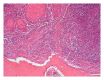

Infections are increasingly considered as potential trigger for carcinogenesis apart from risk factors like alcohol and tobacco. The discussion about human papilloma virus (HPV) in oral squamous cell carcinoma (OSCC) points at a general role of infection for the development of oral carcinomas. Furthermore, first studies describe a correlation between chronic periodontitis and OSCC, thus, characterizing chronic inflammation as being a possible trigger for OSCC. In front of this background, we present four well-documented clinical cases. All patients showed a significant anatomical relation between OSCC and clinical signs of chronic periodontitis. The interindividual differences of the clinical findings lead to different theoretical concepts: two with coincidental appearance of OSCC and chronic periodontitis and two with possible de novo development of OSCC triggered by chronic inflammation. We conclude that the activation of different inflammatory cascades by chronic periodontitis negatively affects mucosa and bone. Furthermore, the inflammatory response has the potential to activate carcinogenesis. Apart from a mere coincidental occurrence, two out of four patients give first clinical hints for a model wherein chronic periodontitis represents a potential risk factor for the development of OSCC.